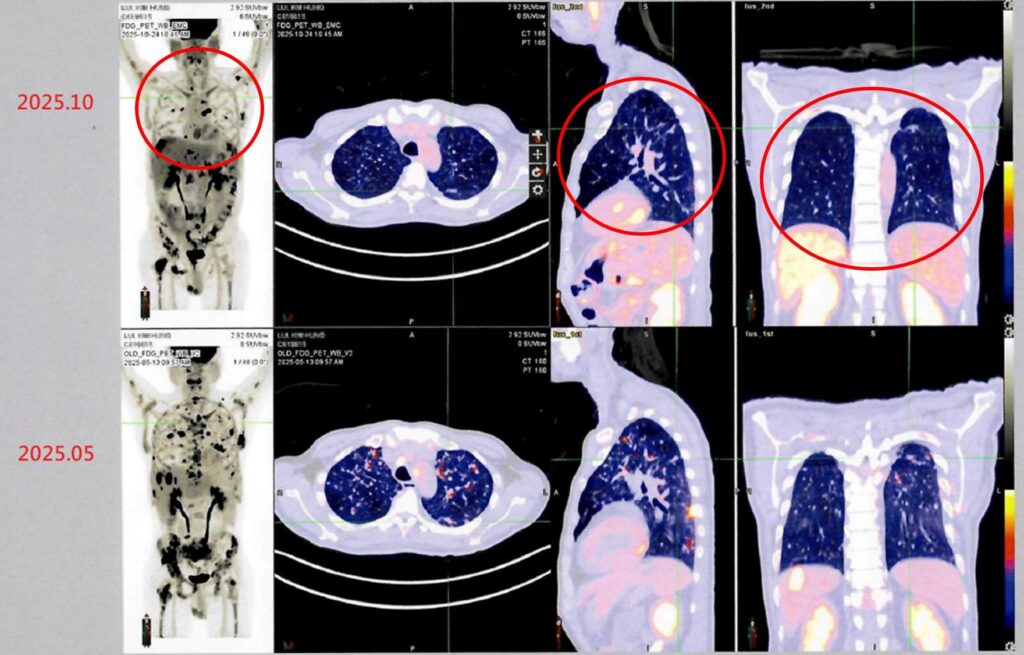

病人接受自體免疫細胞治療(DC-CIK)後,從治療前後影像資料對比(紅圈處),可發現癌細胞減少許多,顯示病情穩定。(照片由衛生福利部雙和醫院提供)

衛生福利部雙和醫院有位來自香港的男性病患(50歲)。他於2024年在香港被診斷出罹患第四期肺癌,歷經多次傳統化療與標靶治療後,為尋求新的治療機會,他評估後決定來台灣進行自體免疫細胞治療(DC-CIK)。經過半年整合療程後,最新影像檢查顯示病情穩定,疼痛症狀明顯獲得緩解,體能與生活品質大幅提升。